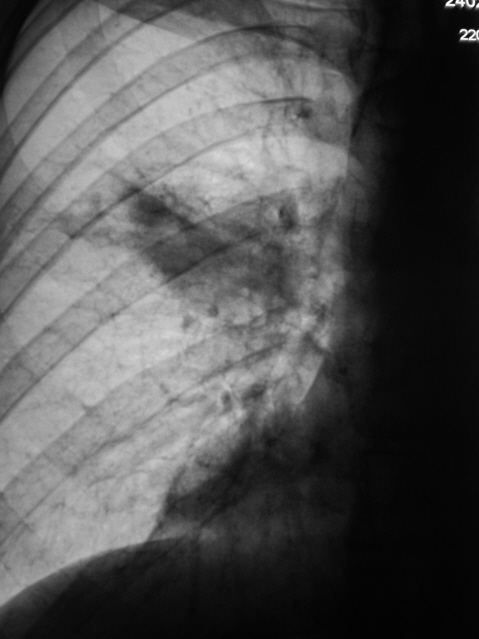

"ВИЧ - носитель" направлен на рентгеновское исследование органов грудной полости с диагнозом "ПНЕВМОНИЯ".

Пневмония произведено стандартное рентгенологическое исследование.

Рентгенограммы в стандартных проекциях.

Пока на данном этапе тянет на "прикорневую пневмонию с вовлечением S6", может и туберкулез выплыть. Нужны анализы и время.

О туберкулёзе тоже думали, и с учетом локализации, и с участившимися случаями "ВИЧ + туберкулёз".

а на томограммах вовсе узлом смотрится... и сочетание "ВИЧ+опухоль" тоже не редкое...

Пожалуй стоит пролечить пневмонию и сделать контроль

"Пневмонию" уже лечат.